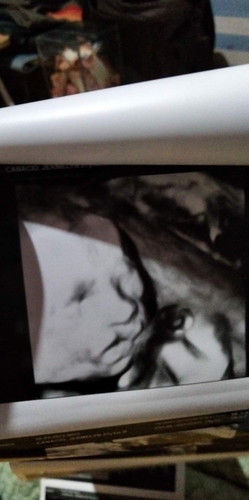

Sino po nakaranas ng ganito sa baby nila ? Unilateral Cleft lip po daw sabi ni Ob ko. Tama po ba to?